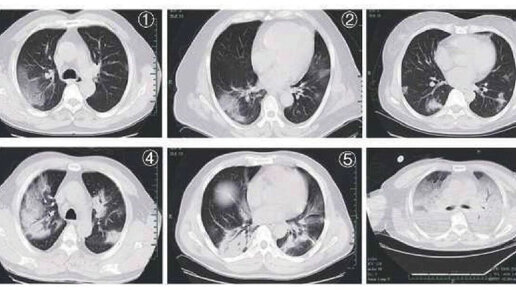

Компьютерная томография позволяет обнаружить специфические изменения, даже при отсутствии симптомов ковид. На КТ-изображениях вирус может проявляется в виде двустороннего затемнения («матовая стенка») и легочных уплотнений. Также на ранней стадии выявления вируса появляются узловатые затемнения, периферическая локализация, симптом «булыжной мостовой». Одним из признаков проявления коронавирусной инфекцией может служить и одиночное узловое затемнение на легочной ткани. У некоторых пациентов именно этот признак был выявлен на ранней стадии заболевания, когда еще не появились клинические признаки...

КТ при covid-19

Кт-признаки, объем поражения и исходы.